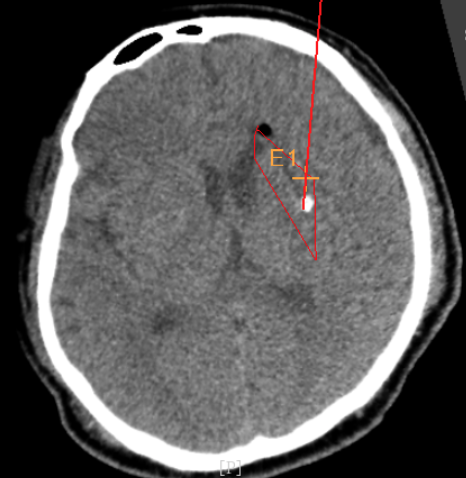

術(shù)前CT:血腫已經(jīng)液化,但仍有占位效應(yīng)

手術(shù)日當(dāng)天,醫(yī)生團(tuán)隊(duì)通過手術(shù)計(jì)劃系統(tǒng)為患者制定手術(shù)靶點(diǎn)及最安全的入顱路徑,隨后將手術(shù)規(guī)劃導(dǎo)入手術(shù)室的機(jī)器人當(dāng)中。

術(shù)前韓帥醫(yī)生使用“睿米”制定手術(shù)規(guī)劃

手術(shù)規(guī)劃在機(jī)器人軟件上制定完成

韓帥醫(yī)生借助機(jī)器人操作平臺順利抽出血性液體15ml,與術(shù)前軟件計(jì)算的血腫量完全一致,手術(shù)在30分鐘內(nèi)順利完成。